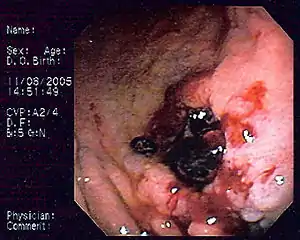

These lymphomas are difficult to differentiate from gastric adenocarcinoma. The lesions are usually ulcers with a ragged, thickened mucosal pattern on contrast radiographs.

The diagnosis is typically made by biopsy at the time of endoscopy. Several endoscopic findings have been reported, including solitary ulcers, thickened gastric folds, mass lesions and nodules. As there may be infiltration of the submucosa, larger biopsy forceps, endoscopic ultrasound guided biopsy, endoscopic submucosal resection, or laparotomy may be required to obtain tissue.